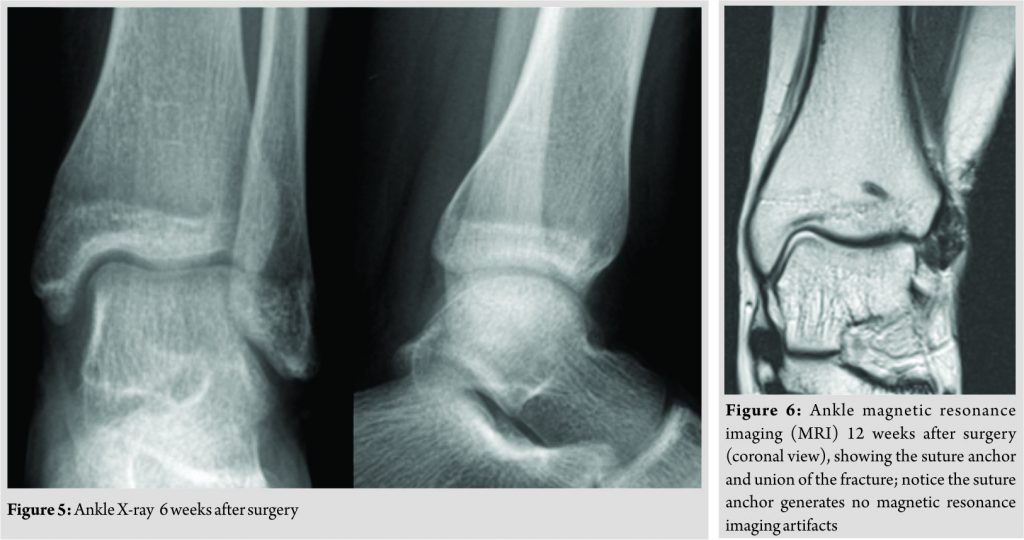

An anterior ankle arthrotomy was performed through a longitudinal two-centimeter incision, and the tissues were dissected between the peroneal muscles and extensor tendons. On inspection, the fracture site was filled with fibrous tissue, and there was gross mobility between the two bony fragments. The fracture line was debrided, and the bone borders were curetted and drilled with a smooth K-wire to enhance the migration of mesenchymal cells into the fracture site. Fixation was obtained using a soft suture anchor– JuggerKnot Soft Anchor 1.4 Short (Biomet, Warsaw, USA). The patient started partial weight-bearing immediately and by 6 weeks post-operative–as the X-rays appeared normal (Fig. 5) –she progressed to full weight-bearing. At 12-weeks postoperative, solid union was confirmed with a magnetic resonance imaging (Fig. 6) and she was allowed to return to sports. With >3 years of follow-up, she is pain free, has normal ankle range of motion and still maintains her sporting activity at the same level as before.